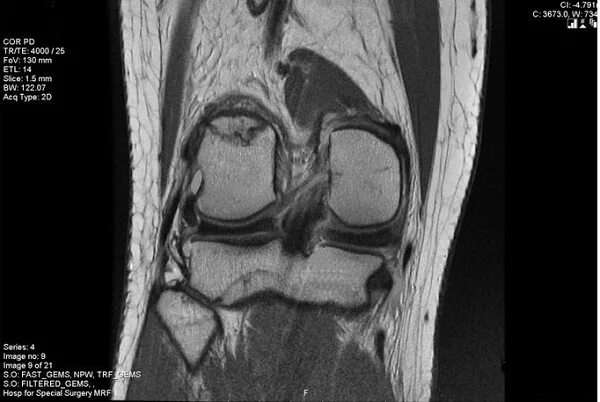

Мрт при боли в суставах